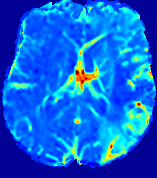

Figure 4: PIANO feature maps for another patient in the ISLES 2017 training set, where the lesion is located in the right hemisphere. Top row: segmented stroke lesion region (white) on different slices. The corresponding slices for the PIANO feature maps are shown in the following rows.

For a better insight into an estimated velocity field 𝐕𝐕{\bf{V}} and diffusion field 𝐃𝐃{\bf{D}}, we compute the following maps: (1) 𝐕rgbsubscript𝐕𝑟𝑔𝑏{\bf{V}}_{rgb}: Color-coded orientation map of 𝐕=(Vx,Vy,Vz)T𝐕superscriptsuperscript𝑉𝑥superscript𝑉𝑦superscript𝑉𝑧𝑇{\bf{V}}=(V^{x},V^{y},V^{z})^{T}, obtained by normalizing 𝐕𝐕{\bf{V}} to unit length and mapping its 3 components to red, green, blue respectively; (2) 𝐕2subscriptnorm𝐕2\|{\bf{V}}\|_{2}: 222 norm of 𝐕𝐕{\bf{V}}; (3) D𝐷D: scalar field in Eq. 5.

Fig. 3 and Fig. 4 show the PIANO feature maps estimated from two ISLES 2017 patients: all are highly consistent with the lesion in both cases. Details of the blood flow trajectories are revealed in 𝐕rgbsubscript𝐕𝑟𝑔𝑏{\bf{V}}_{rgb} by the ridged patterns and the sharp changes of colors in the unaffected (right) hemisphere, while the flat patterns appearing within the lesion provide little directional information about the velocity and indicate low velocity magnitudes. Velocity magnitudes are more directly visualized via 𝐕2subscriptnorm𝐕2\|{\bf{V}}\|_{2}, from which one can easily locate the lesion where 𝐕2subscriptnorm𝐕2\|{\bf{V}}\|_{2} is low. D𝐷D also indicates lower diffusion values in the lesion, though with less contrast potentially due to the fact that it captures the accumulated effect of CA diffusion at the voxel-level.